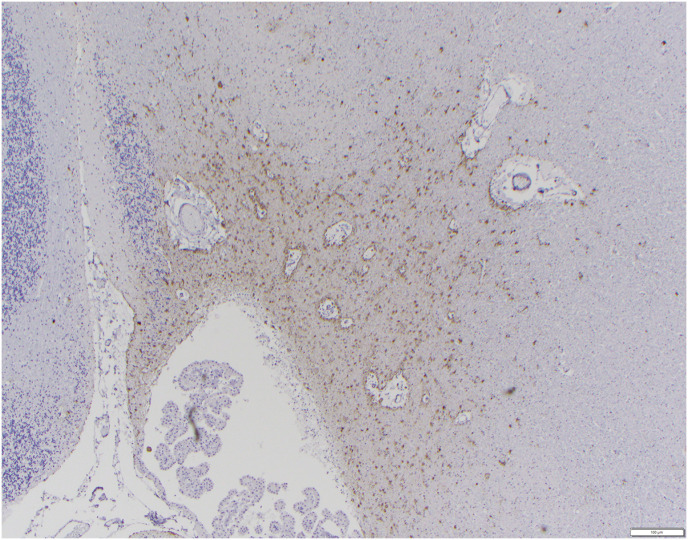

Case presentation: This report aims to describe the AD-like neuropathology in the brain of a 37-year-old female baboon (Papio hamadryas), which at the time of her death made her the oldest hamadryas baboon at any member institution of the Association of Zoos and Aquariums. A diagnostic necropsy was performed, and the brain was evaluated for neurodegenerative disease. Frequent amyloid-β deposits were identified, consistent with what has been described in other geriatric nonhuman primates. Phospho-tau pathology, including neurofibrillary tangles, a feature not well-described in other primate models, was also abundant.

Conclusions and relevance: Our results suggest that more detailed, prospective, longitudinal studies are warranted utilizing this particular species to see if they represent a viable model for human brain aging.